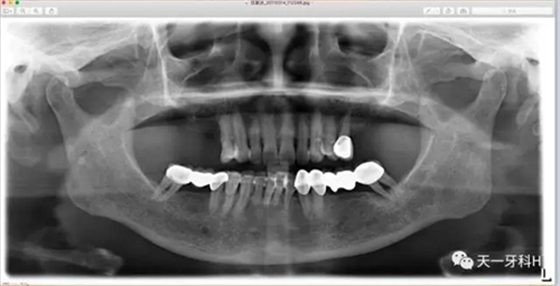

2011年3月3日拍攝:

2011年3月3日,這個患者又來到了診所,此時的她上頜的烤瓷橋已經(jīng)沒有了,做基牙的牙齒右上七和右上五沒有了,右上四遠中的牙槽骨也已經(jīng)破壞到根尖四分之一了,左上八沒有了,只剩下左上五,下頜烤瓷橋雖然還在,但左下八近中的牙槽骨吸收也到達根尖了。